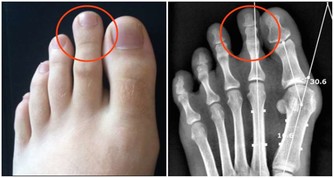

5、過敏

防禦系統要將血液裡的毒素排出體外,因此皮膚會過敏,而我們現在大多數人用抗過敏藥、塗藥膏、

將本來要通過皮膚排出來的毒素,再度壓進身體裡。